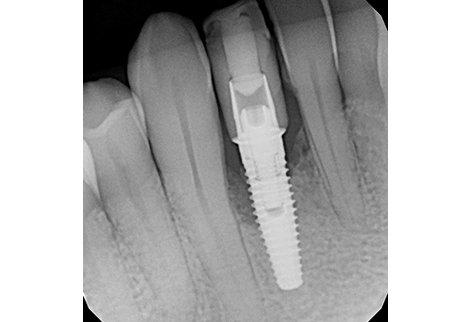

Implant Replacement:

At 4 months post-grafting, a CBCT scan demonstrated sufficient bone volume and density to support a new implant at site #42. A 3.5 x 10 mm narrow-diameter Nobel Biocare TiUltra CC implant was placed at 25 Ncm torque, with ISQ testing measuring 68 and a 3.6 x 3 mm healing abutment inserted at 15 Ncm torque. After 4 months of osseointegration, the implant was restored with a screw-retained zirconia crown, using on-brand Nobel Biocare prosthetic components.

1-Year Follow-Up

Outcome:

At the 1-year follow-up, the implant was functional with healthy surrounding tissues and no signs of inflammation. The implant–bone crestal bone level was maintained due to improved prosthetic design: good emergence profile, short well-positioned contact areas, and screw-retained prosthetic with proper contours.